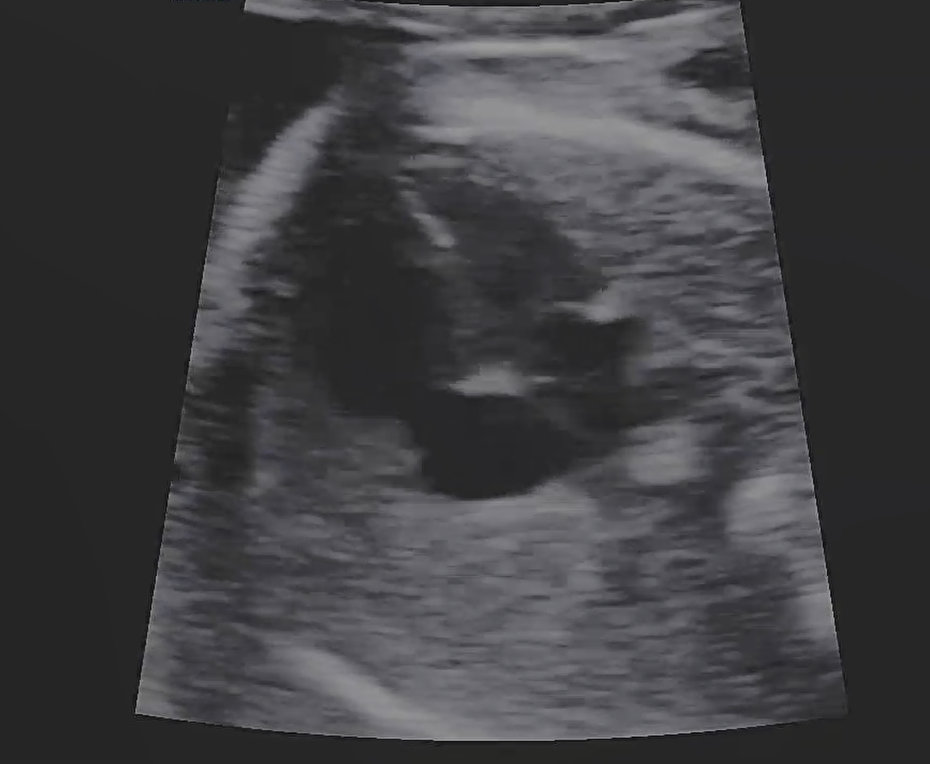

21주 5일, 정밀 초음파 검사가 있는날이었다.

정밀 초음파는 기관들이 잘 형성되어 있는지 초음파로 확인 하는 것이라고 했다.

눈, 코, 입, 심장, 손가락, 발가락 등등 하나하나 확인했다.

포도가 돌아누워서 마지막까지 얼굴을 잘 안보여줘서 코뼈를 못봤다.

배를 흔들어봐도 더 숨기만 했다.

코뼈는 다음에 봐주시기로 했다.

코뼈 빼고 나머지는 다 정상이라고 하셨다.